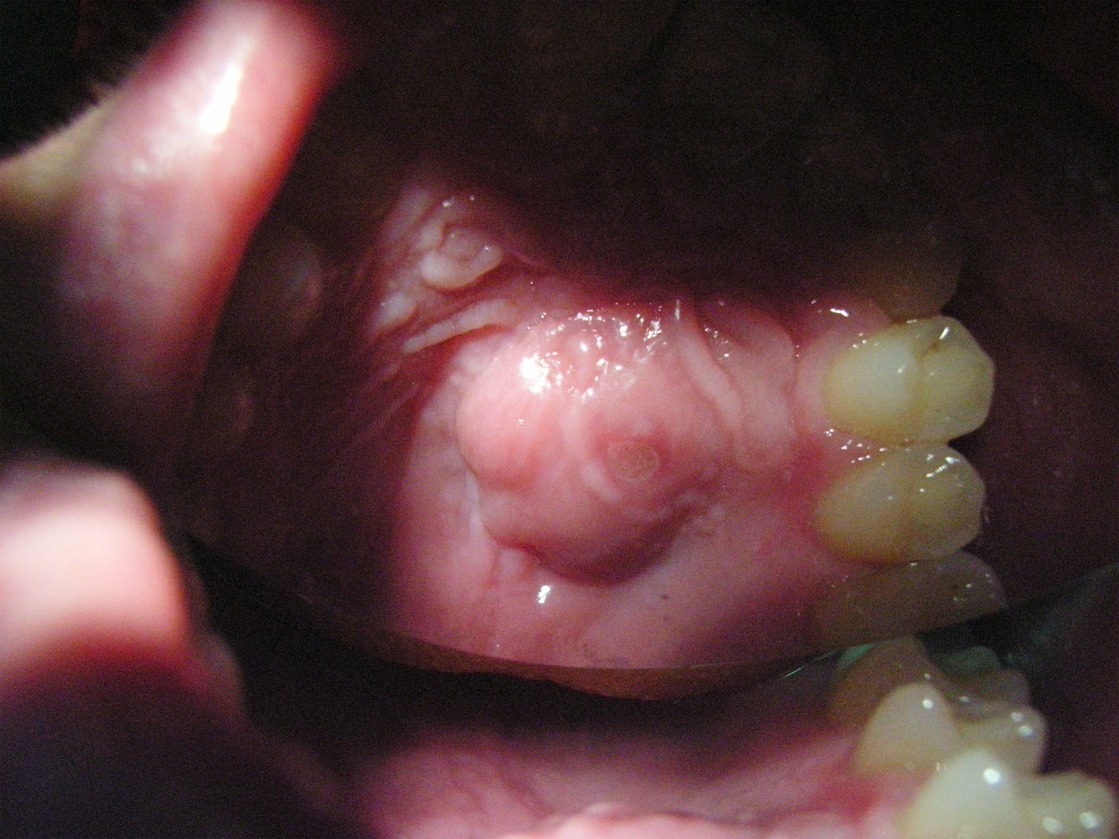

Caro Signor Vincenzo...le voglio spiegare alcune cose: ...i microbi stanno e vivono nella radice come in una "provetta" trovando un terreno ideale...sono microbi cattivi...anaerobi e gram negativi...le loro tossine escono fuori dal dente e causano una zona di osteolisi ( quella macchia nera che vede in radiografia) per stimolazione degli osteoclasti che distruggono l'osso (per intenderci gli osteoblasti sintetizzano e formano osso...gli osteoclasti lo distruggono)...una volta curata e sterilizzata e sigillata in modo perfetto la radice...queste tossine scompaiono dall'osso...perchè non ci sono più i microbi a sostenerle da dentro la radice...e il granuloma ( o la cisti) si riassorbe da solo...poi ci sono altri granulomi ( o anche Cisti) che non hanno nulla a che vedere con le infezioni della radice...e che prendono origine (ma più comunemente sono cisti...ma è difficile differenziare una piccola cisti da un piccolo granuloma in modo certo...in ogni caso la terapia è la stessa e le cause ed i principi sono i medesimi)...prendono origine dicevo da residui di cellule embrionali dette del Malassetz...che con l'eruzione del dente scompaiono...ma a volte..raramente ne rimangono dei residui che può per noxe di vari tipo danno origine alla zona di osteolisi...poi ci sono cisti non odontogene ossia che non prendono origine dai canali ..rarissime se non eccezionali in questa zona da lei descritta poi ci sono altre formazioni, tra cui le cisti non odontogene (che non prendono origine da un dente) per la cui diagnosi è necessario un prelievo bioptico .per chiudere...basta, di regola dopo accurata diagnosi se confermata la cisti solo curare la radice per via ortograda o chirurgica retrograda...BENE!. guardi questa foto che le invio ...per completare la risposta alla sua domanda, due osservazioni nel suo caso, con una GROSSA OSTEOLISI e con MOBILITA' dei denti è doveroso fare un prelievo citologico con "puntura ed aspirazione" per confermare la diagnosi ed eventualmente una TAC mirata...cordialmente